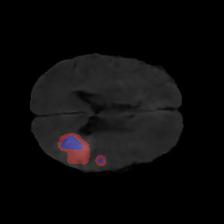

Brain tumor segmentation. Segmenting tumors in brain is challenging due to the high variance in appearance and shape of the tumors [28]. We use a subset of the 2017 Brain Tumour Image Segmentation (BraTS) dataset [29, 26]. It contains multi-parametric 3D MRI scans. The segmentation masks include (possibly overlapping) three classes of tumor. The 3D scans are split into 2D image slices, and only images that contain at least one tumor class are retained. Figure 7 shows three MSGNet generated samples as well as the corresponding masks. Since MSGNet adheres to the underlying relationships between various classes, we see that the generated images and the masks for different tumor classes are in line with the images and masks from the training set. In general, MSGNet rarely generated erroneous samples; we found roughly one sample per 3000 generations that could be rejected. Similar to the malaria experiment, we observed an improvement of 3.1% () in -score on the validation set.

A subset of the BrATS dataset was used. We used the images accompanied by segmentation layouts from the FLAIR and T1Gd modes. The segmentation layouts showed the sub-regions for three different classes: GD-enhancing tumor, the peritumoral edema, and the necrotic and non-enhancing tumor core. The brain and the background were treated as an additional class. We refer to [32] for further details. For the two modes, the background has been modelled using two different classes. We only considered half of the 155 slices, i.e., we took only the even-numbered slices and out of those we discarded the slices that did not include one of the previously mentioned tumor-classes in order to create a more balanced dataset. This resulted in 20,000 images that were further augmented with 6,000 MSGNet generated images. Example generations of the masks as well as the images are shown in Figure 12.